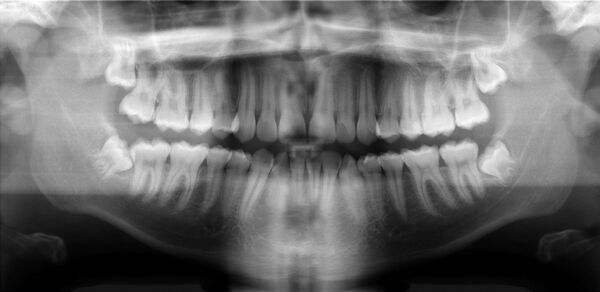

Ортопантомография (от греч.: orthos — прямой, правильный, pan — всё, tomos — ломоть, отрезанный кусок и grapho — писать, рисовать) — особый вид рентгеновской съёмки костей лицевого скелета, при котором они «развёртываются» в одну плоскость[1]. Другими словами рентгенологическое исследование в стоматологии, челюстно-лицевой хирургии, косметологии, позволяющее получать развёрнутое изображение всех зубов с челюстями, прилежащими отделами лицевого скелета. Является первичным рентгенологическим исследованием[2].

Галерея